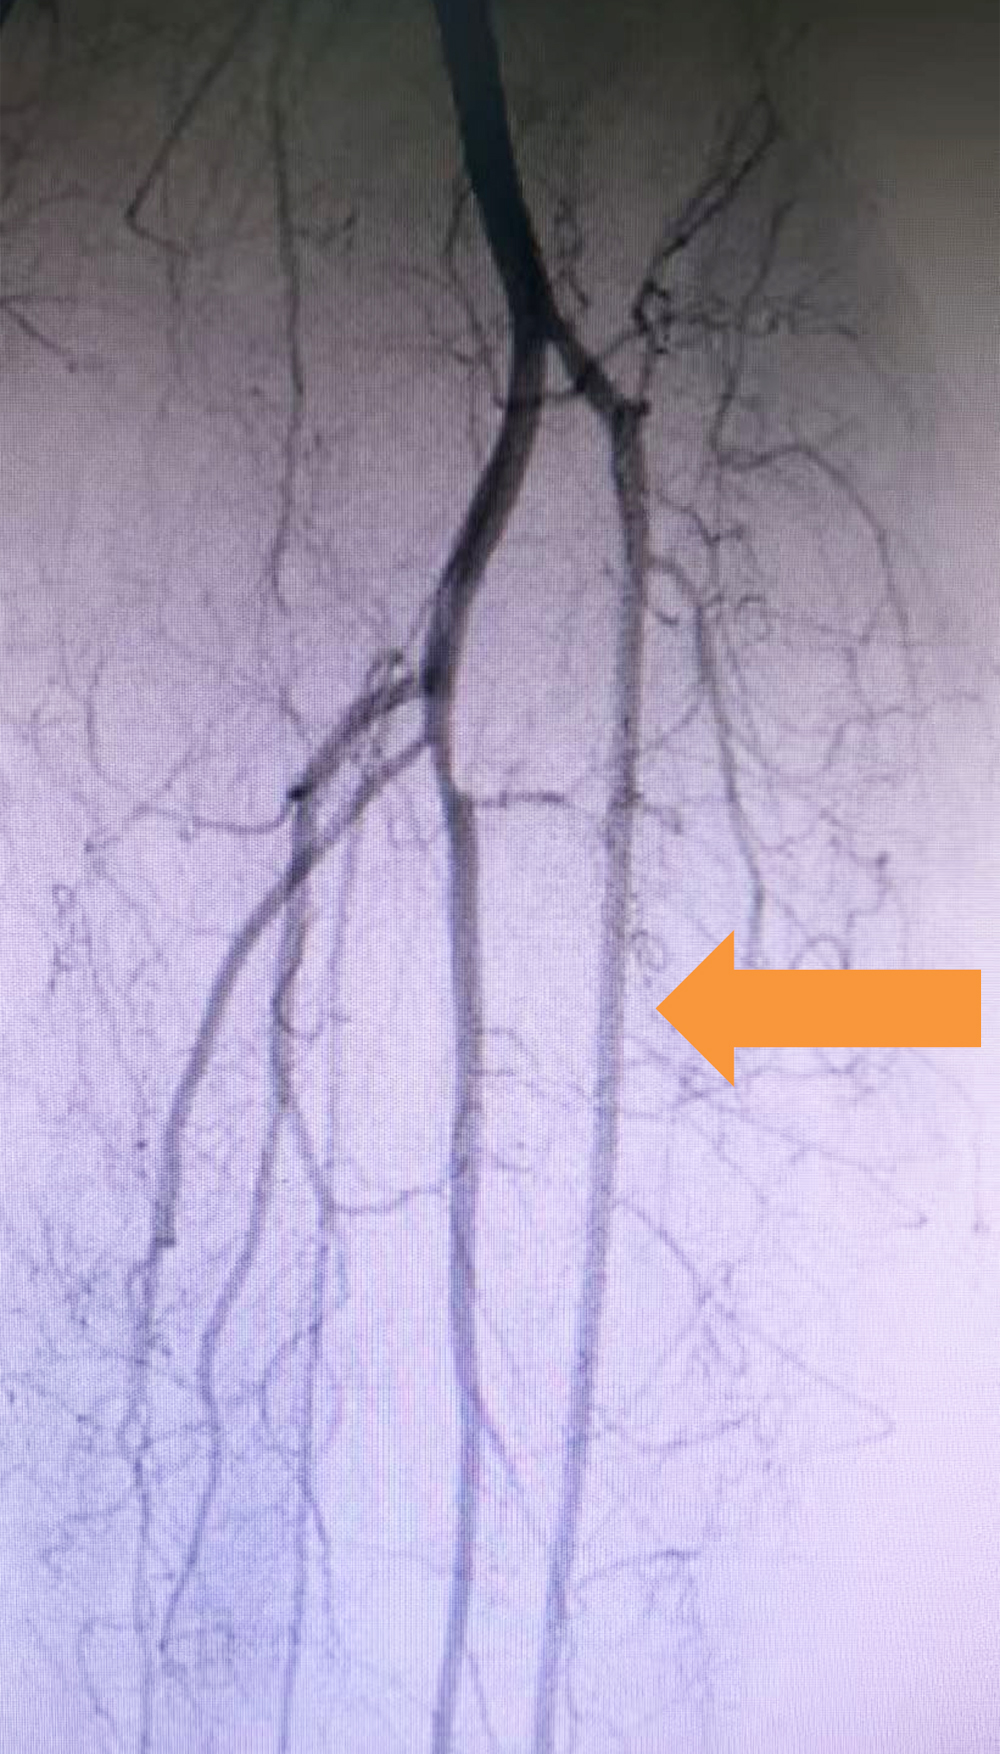

取栓后 左下肢动脉造影,显示膝下动脉血流恢复